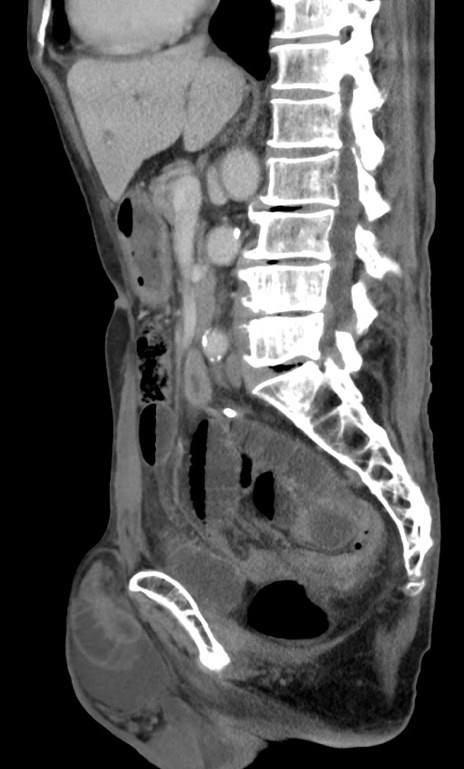

症例3(矢状断像)

【症例】 70歳代男性

【主訴】右鼠径部腫瘤、疼痛

【現病歴】本日朝より上記主訴あり、受診。

【既往歴】膀胱癌にて膀胱全摘、両側尿管皮膚瘻

【データ】WBC 5600、CRP 0.56